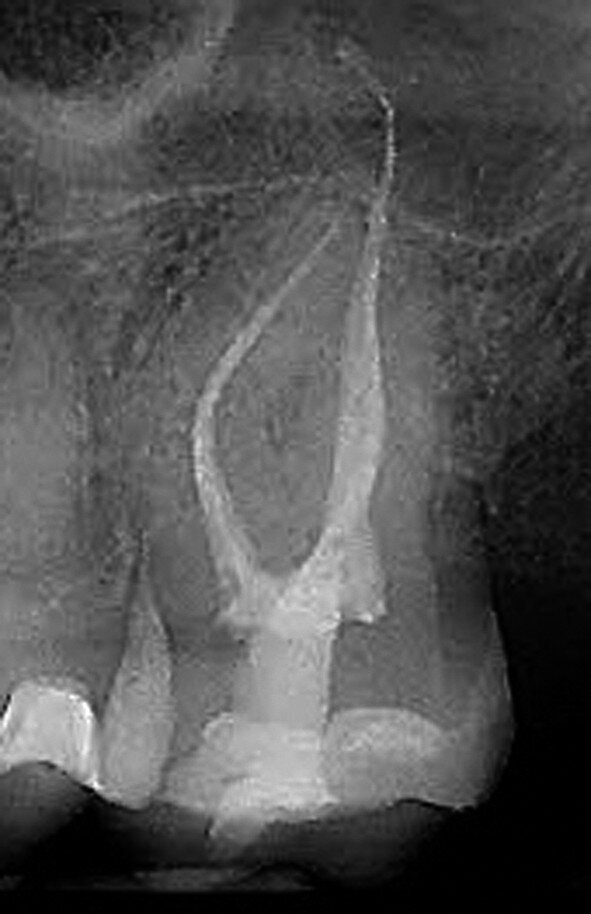

Figs. 12a–d : Depuis la gauche : Cas de l’auteur : dent

37 présentant une fracture radiculaire ; cette dent

montée dans un modèle en plâtre-pierre après extraction,

avec impression du guide de forage CTGEA

monté et du premier foret en place ; les deux

petits orifices d’accès préparés au moyen du guide

de forage ; et la radiographie postopératoire montrant

l’adaptation des cônes dans les canaux après leur négociation et leur mise en forme.